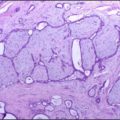

Central nervous system white matter lesions. 45-year-old male. T2 Brain MR image showed widespread, punctuated and confluent white matter lesions from periventricular to subcortical spaces. These lesions are associated with severe axonal injury (gliosis).Fibrosis: a key feature of Fabry disease with potential therapeutic implications. Weidemann F, Sanchez-Niño MD, Politei J, Oliveira JP, Wanner C, Warnock DG, Ortiz A - Orphanet journal of rare diseases (2013). Not Altered. CC.